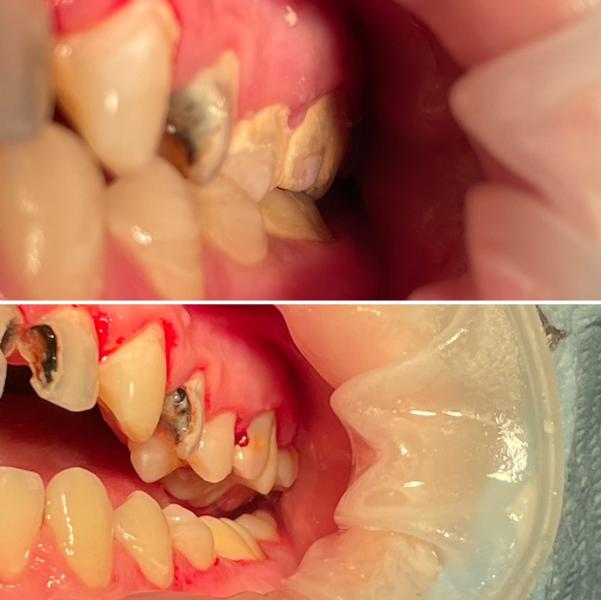

Брезгливым не листать ❌❌❌

Пациент 16лет,мама впервые привела к стоматологу,в полости рта очень плачевное состояние,объяснила маме все,расписала лечение провела проф гигиену(убрала весь налет и камни)

Далее мама отказалась от лечения,говоря что это очень дорого

Что я могу тут сказать?Мне очень жаль мальчика..их лечение не обходилось бы им в такую сумму,если бы она приводила его 2раза в год на санацию,очень надеюсь что они не оставят все так и будут лечить хотя бы один/два зуба в месяц